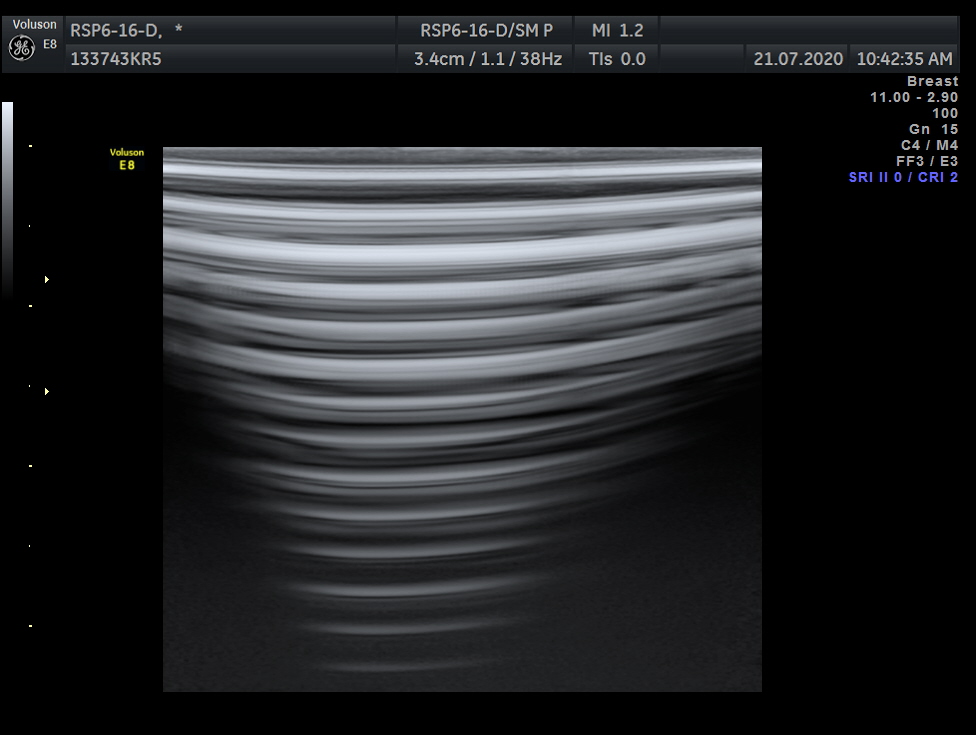

Breast, Small parts, Vascular and Musculoskeletal

Frequency Range: 18 – 6 MHz

GE RSP6-16-D 3D/4D Linear for Breast, Small parts, Vascular and Musculoskeletal

| Type of examination 3D/4D | |